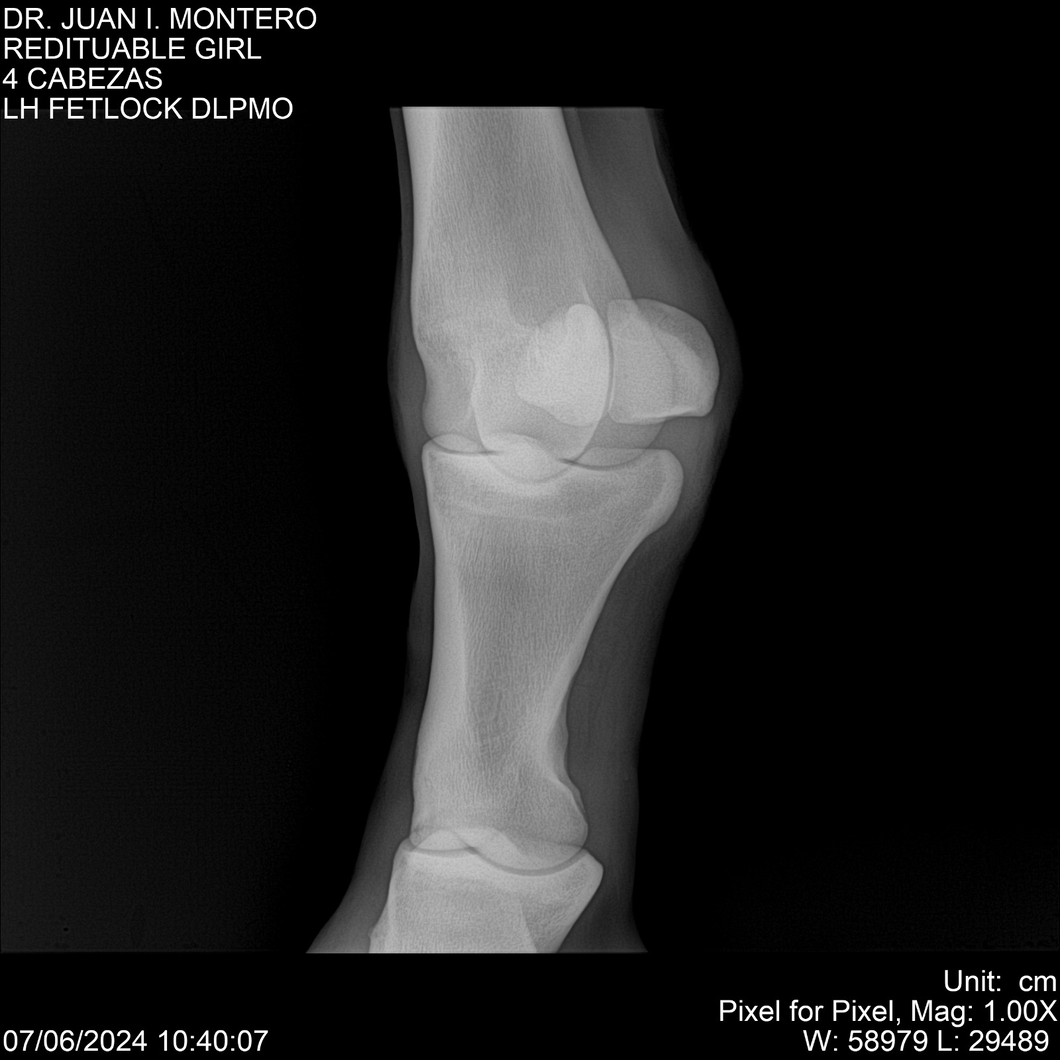

LOTE 19, REDITUABLE GIRL Lote Anterior Volver al remate Lote Siguiente Ficha Contacto Montevideo - Ficha del Lote Identificador: #281096 Categoría: Yeguarizos Montevideo - 79 Visualizaciones ClicData Contacto Empresa: Abelenda N. R., Walter Hugo Nombre*: Teléfono* : E-mail* : Mensaje Enviar Registrese gratis Este contenido Exclusivo está disponible sólo para usuarios registrados Ingresar